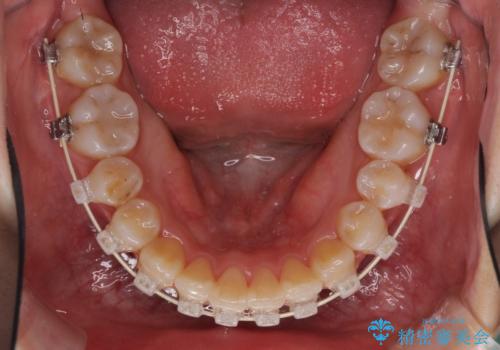

- 矯正装置

- 審美装置

- 2年10ヶ月

犬歯は歯根が太く長いため、移動には時間を要します。しかし、犬歯は機能面から考えて残すことを選択したいため、長期間をかけて治療を行うこととしました。

治療の度に歯列が改善していったため、長期間の治療も楽しく過ごしていいただき、満足のいく仕上がりとなりました。